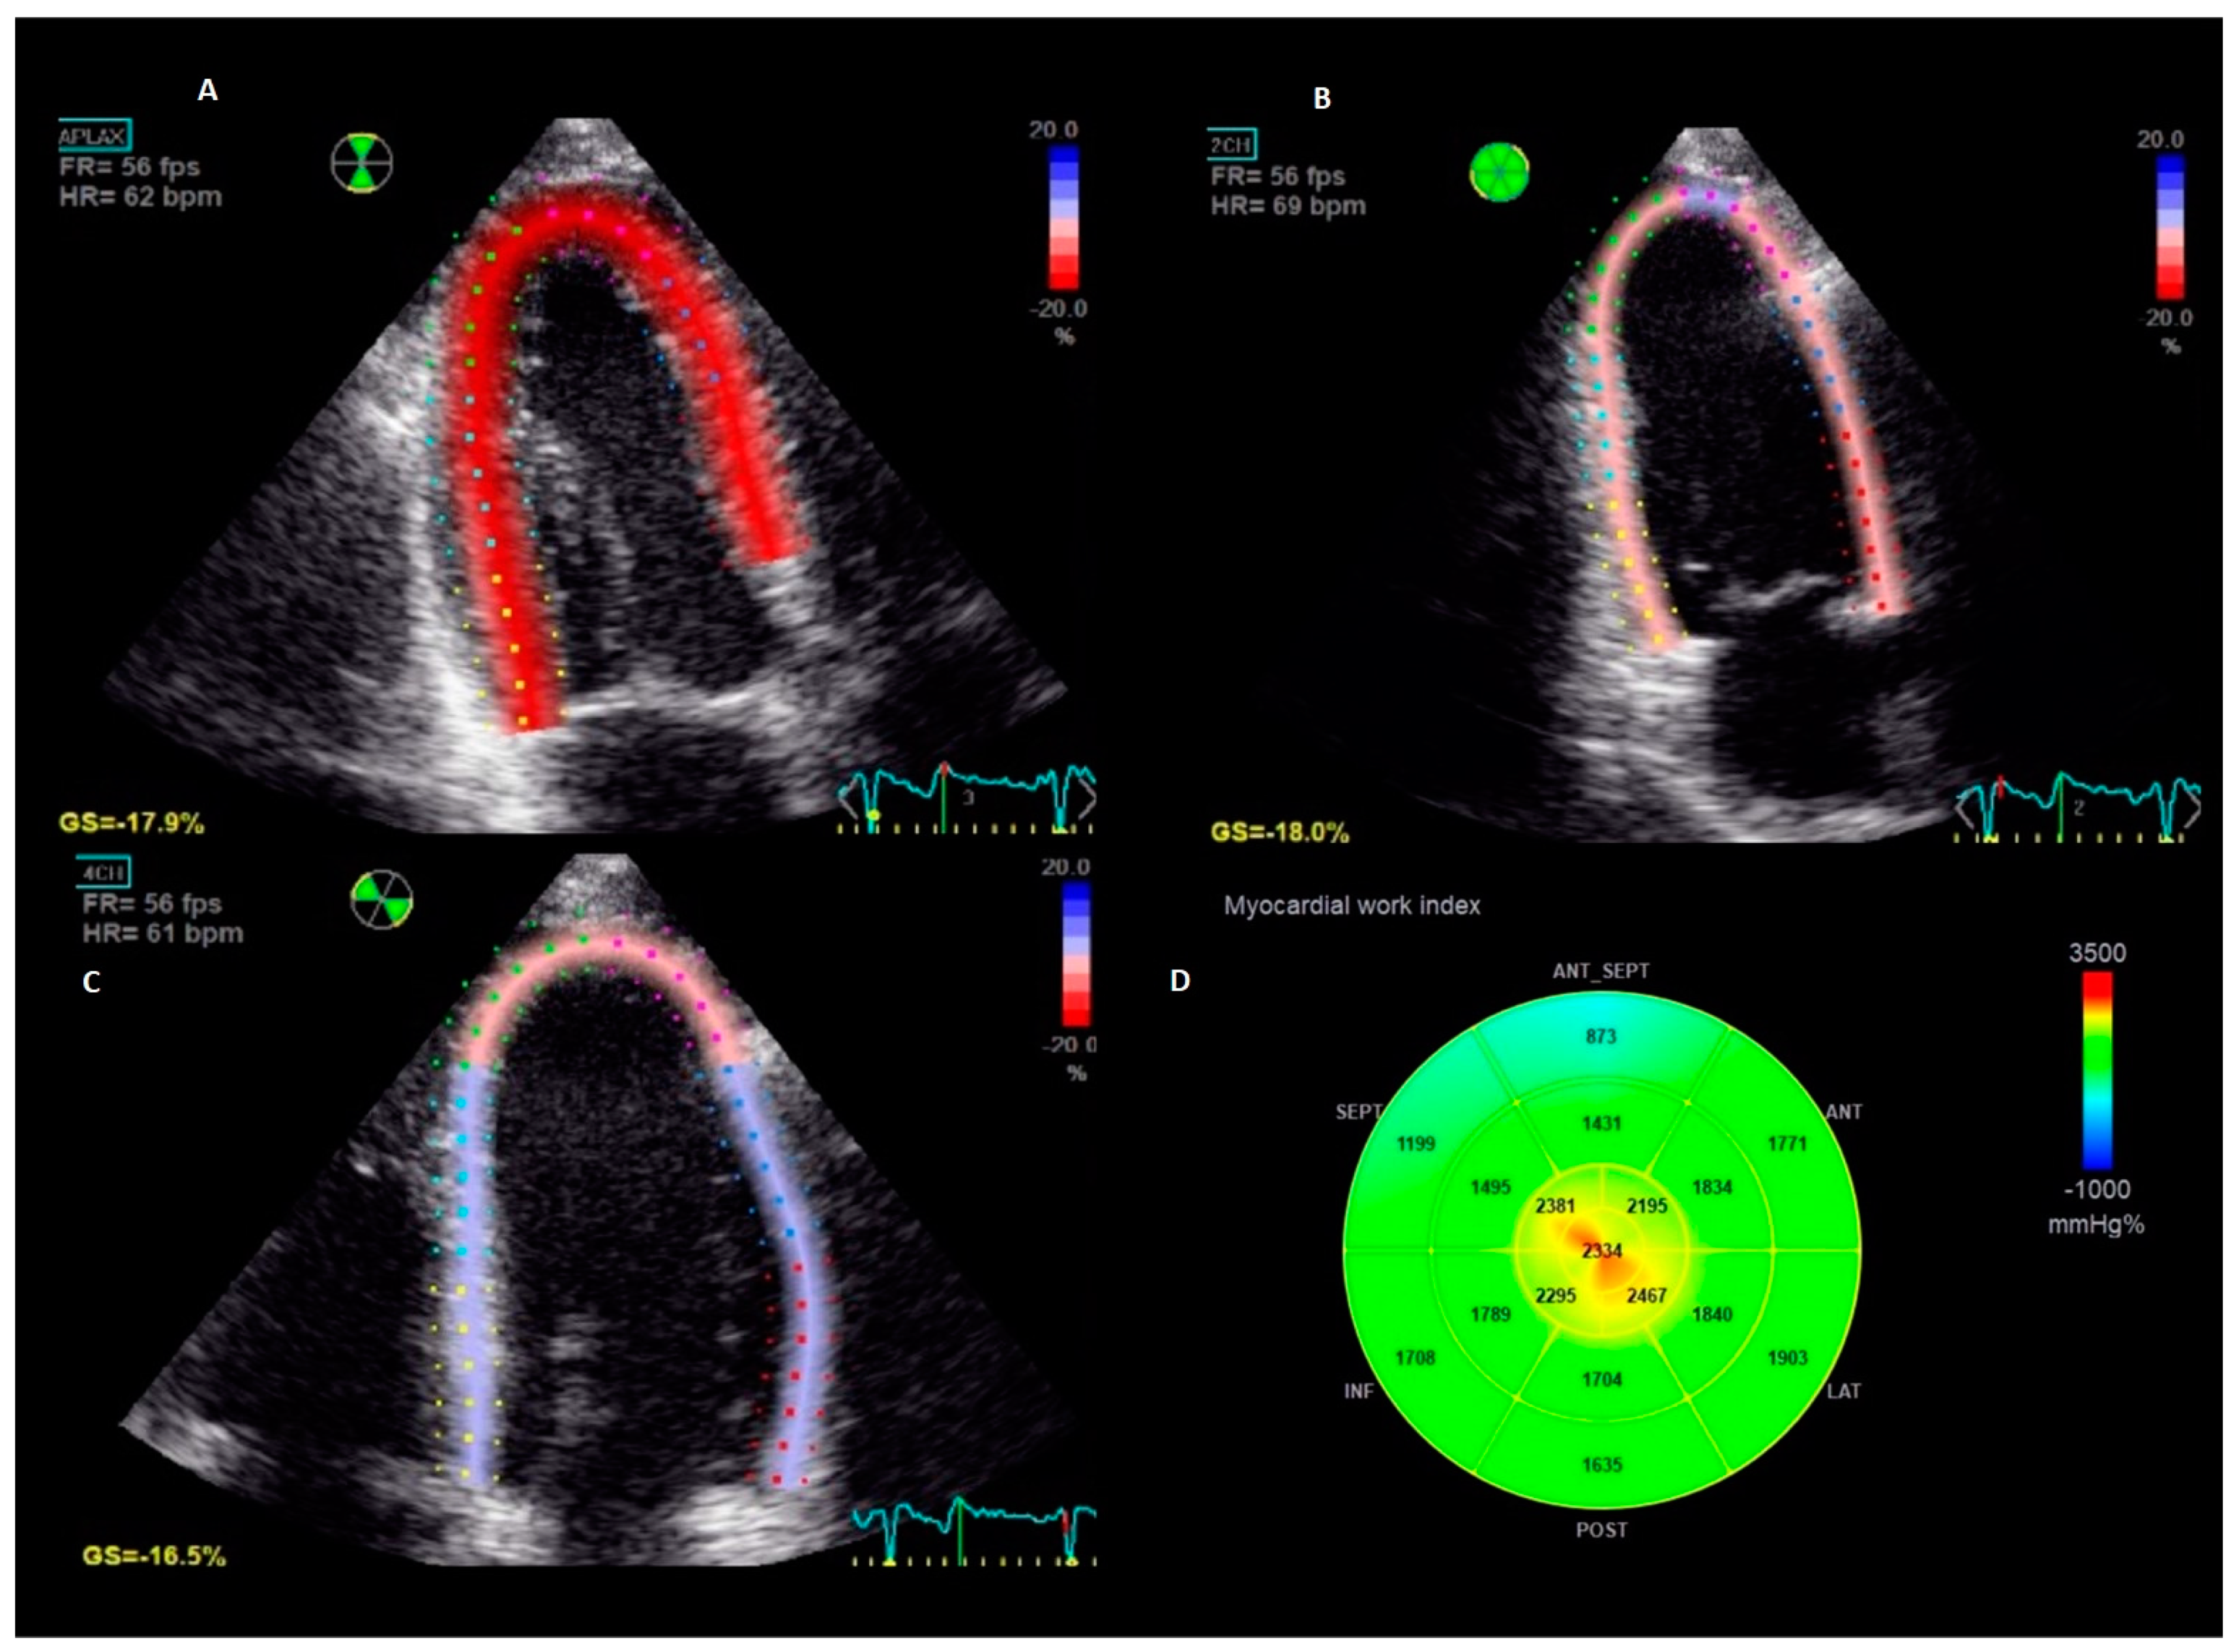

2.5. Myocardial Work Analysis

Two-dimensional speckle tracking analysis was performed offline on a dedicated workstation equipped with EchoPac BT 202 (GE Vingmed Ultrasound, Horten, Norway). Apical two-, three-, and four-chamber views with an optimized frame rate were analysed using the Automated Function Imaging application. GLS was calculated as the average peak systolic negative longitudinal shortening of the 18 LV segments. Since GLS is expressed as a negative percentage, we report the absolute values |x| for a simpler interpretation. Timing of mitral and aortic valve opening and closure were determined using pulsed-wave Doppler signals. The supine brachial BP measured at the end of the echocardiographic examination was used in the calculation of LV myocardial work. By synchronizing longitudinal strain, BP, and timing of valvular events, non-invasive pressure-strain loops (PSL) were provided (Figure 1). The area within the PSL corresponds to a global myocardial work index (GWI), calculated from mitral valve closure to mitral valve opening. In addition, other indices of myocardial work such as global constructive work (GCW, the work performed during LV shortening in systole and LV lengthening during isovolumic relaxation), global wasted work (GWW, myocardial work not contributing to LV ejection due to lengthening in systole and LV shortening during isovolumic relaxation), and global work efficiency (GWE, constructive work divided by the sum of constructive and wasted work) were calculated [23].

Figure 1. Measurement of myocardial work in an individual patient. The figure represents the longitudinal strain imaging from the standard apical-three-chamber (Panel (A)), two-chamber (Panel (B)) and four-chamber (Panel (C)) views and the corresponding bull`s eye of global work index calculated from the area within the pressure-strain loop (Panel (D)).